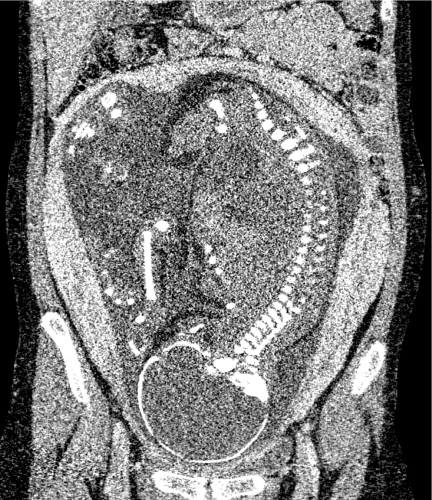

The deep learning reconstruction method (DLR) we first developed is a technique that uses deep learning models trained with low-noise target images to generate high-quality images with reduced noise. As shown in Figure 1, it is now possible to obtain high-quality images by applying a deep learning model to cross-sectional images reconstructed using conventional methods from projection data obtained by CT scanning (2,3). The results shown in Figure 2 confirm that the noise is significantly reduced and higher-quality CT images are obtained compared to images obtained using conventional methods.

Fig. 2: Fetal CT image processed using DLR shows substantial noise reduction compared to the conventional method.